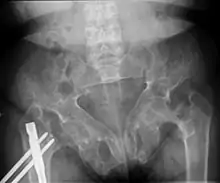

Renal osteodystrophy is usually diagnosed after treatment for end-stage kidney disease begins; however the CKD-MBD starts early in the course of CKD.[1][6] In advanced stages, blood tests will indicate decreased calcium and calcitriol (vitamin D) and increased phosphate, and parathyroid hormone levels. In earlier stages, serum calcium, phosphate levels are normal at the expense of high parathyroid hormone and fibroblast growth factor-23 levels. X-rays will also show bone features of renal osteodystrophy (subperiostic bone resorption, chondrocalcinosis at the knees and pubic symphysis, osteopenia and bone fractures) but may be difficult to differentiate from other conditions. Since the diagnosis of these bone abnormalities cannot be obtained correctly by current clinical, biochemical, and imaging methods (including measurement of bone-mineral density), bone biopsy has been, and still remains, the gold standard analysis for assessing the exact type of renal osteodystrophy.[6][16]